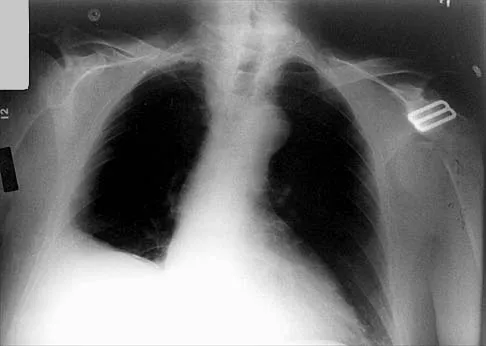

Which of the following findings is seen in the chest radiograph shown in Figure 13?